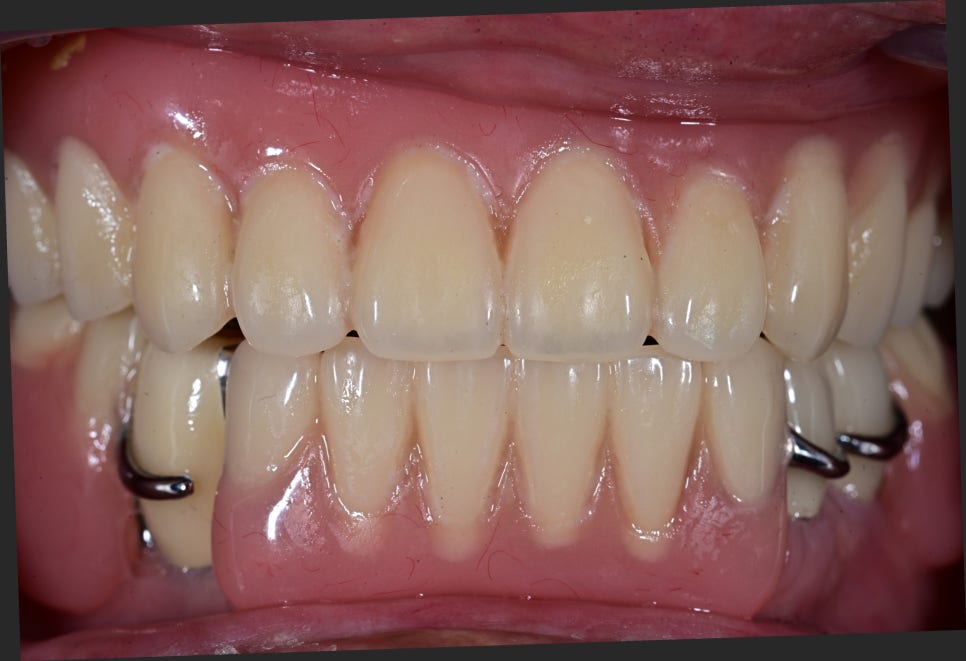

치료 전후 비교

※ 아래 사진은 치료 전후 비교 사진입니다.

– 상악 완전틀니 장착 후 모습

– 하악 임플란트 식립 후 부분틀니 장착 모습

<Before>

<After>